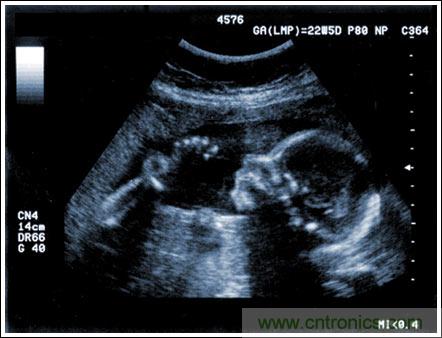

通過發射超聲能量進入人體,接收并處理返回的反射信號,相控陣超聲系統可以生成體內器官和結構的圖像,映射血液流動和組織運動,同時提供高準確度的血流速度信息。傳統設計中,構建這樣的成像系統需要大量的高性能相控陣發射器和接收器,使得車載設備體積龐大且價格昂貴。近年來,隨著集成工藝的進步,設計人員能夠獲得小尺寸、低成本而且高度便攜的成像系統方案,并可達到接近大型成像設備的性能指標。而新的設計挑戰依然存在,即在進一步提高方案集成度的同時提高系統性能和診斷能力。